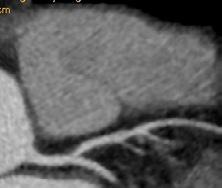

Figura 1. Pacient de 57ani cu simptomatologie acută sugestivă pentru AVC ischemic acut: CT -ul nativ nu a decelat elemente de semiologie sugestive pentru AVC ischemic acut (A), însă secvențele IRM au evidențiat o arie în hipersemnal FLAIR (B) și cu restricție de difuzie (C) localizată occipital paramedian dreapta, sugestivă pentru AVC ischemic acut (Spitalul Clinic de Urgență „Prof. N. Oblu“, Iași)

În contrast, imagistica prin rezonanță magnetică, în special secvențele de difuzie, oferă o sensibilitate superioară pentru detectarea precoce a infarctului ischemic,

fiind capabilă să identifice modificări la nivel celular la doar câteva minute după debutul simptomelor (Figura 1) (Mouridsen et al., 2020), (Nukovic et al., 2023). De asemenea, IRM este capabilă să ofere o evaluare superioară a integrității parenchimului cerebral, a viabilității țesutului și a extinderii leziunii ischemice, facilitând o caracterizare mai detaliată a AVC-ului ischemic (Cortés-Albornoz et al., 2025).